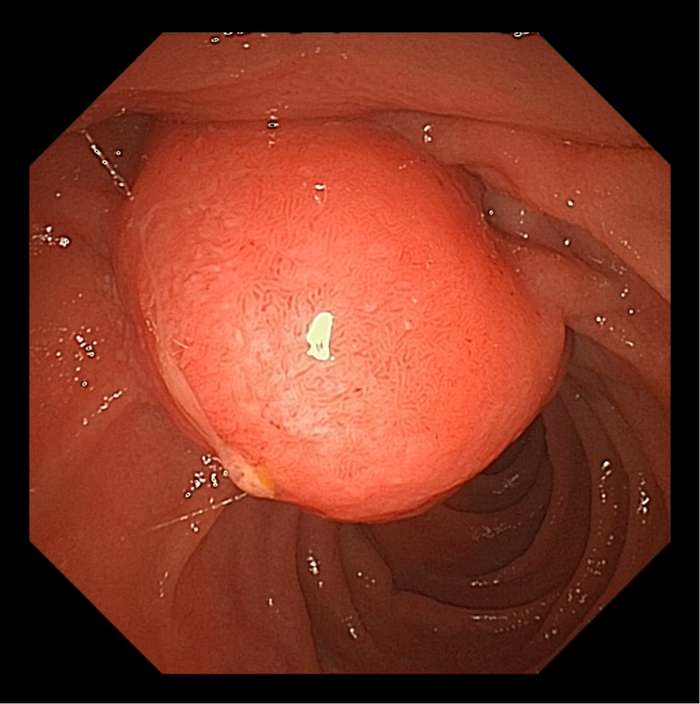

患者男,65岁。于十二指肠内侧找见主乳头,乳头呈鼻型,开口呈绒毛样。胆管狭窄导致反复超选导丝无法进入,后使用一次性粘膜切开刀,沿胆管方向行预切开,再次插管导丝进入胆管,注入少量造影剂,胆管显彰。

患者于三月后更换胆管支架,十二指肠镜应用操作如图所示: